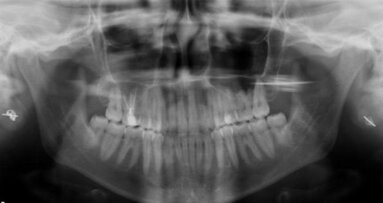

WUHAN, China: Patients frequently suffer from postoperative pain, which is why information about precise medication is urgently needed by dentists today. In a recent study, an artificial neural network (ANN) model was used to predict pain after root canal treatment (RTC), which is of clinical importance for doctors in order to improve the quality of treatment, establish optimised treatment plans and reduce the occurrence of medical disputes.

It is reported that ANN may make it possible to identify important variables and predict post-treatment pain with high accuracy. This study by researchers from Wuhan University aimed at evaluating the accuracy of the back propagation (BP) artificial neural network model for predicting postoperative pain after RCT.

The BP neural network model was developed using MATLAB 7.0’s neural network toolbox, and a functional projective relationship was established between 13 parameters, (including personal factors, inflammatory reaction factors and operative procedure factors) and the postoperative pain experienced by the patient after RCT.

This neural network model was trained and tested based on data from 300 patients who underwent RCT. Of these cases, 210, 45 and 45 were allocated as the training, data validation and test samples, respectively, to assess the accuracy of prediction. Study authors Xin Gao and Xing Xin and their team found that the accuracy of this BP neural network model was 95.6% for the prediction of postoperative pain after RCT.

The scientists concluded that the BP network model could be used to predict postoperative pain after RCT and showed clinical feasibility and application value. Therefore, the proposed method could be used as a clinical reference in the future.